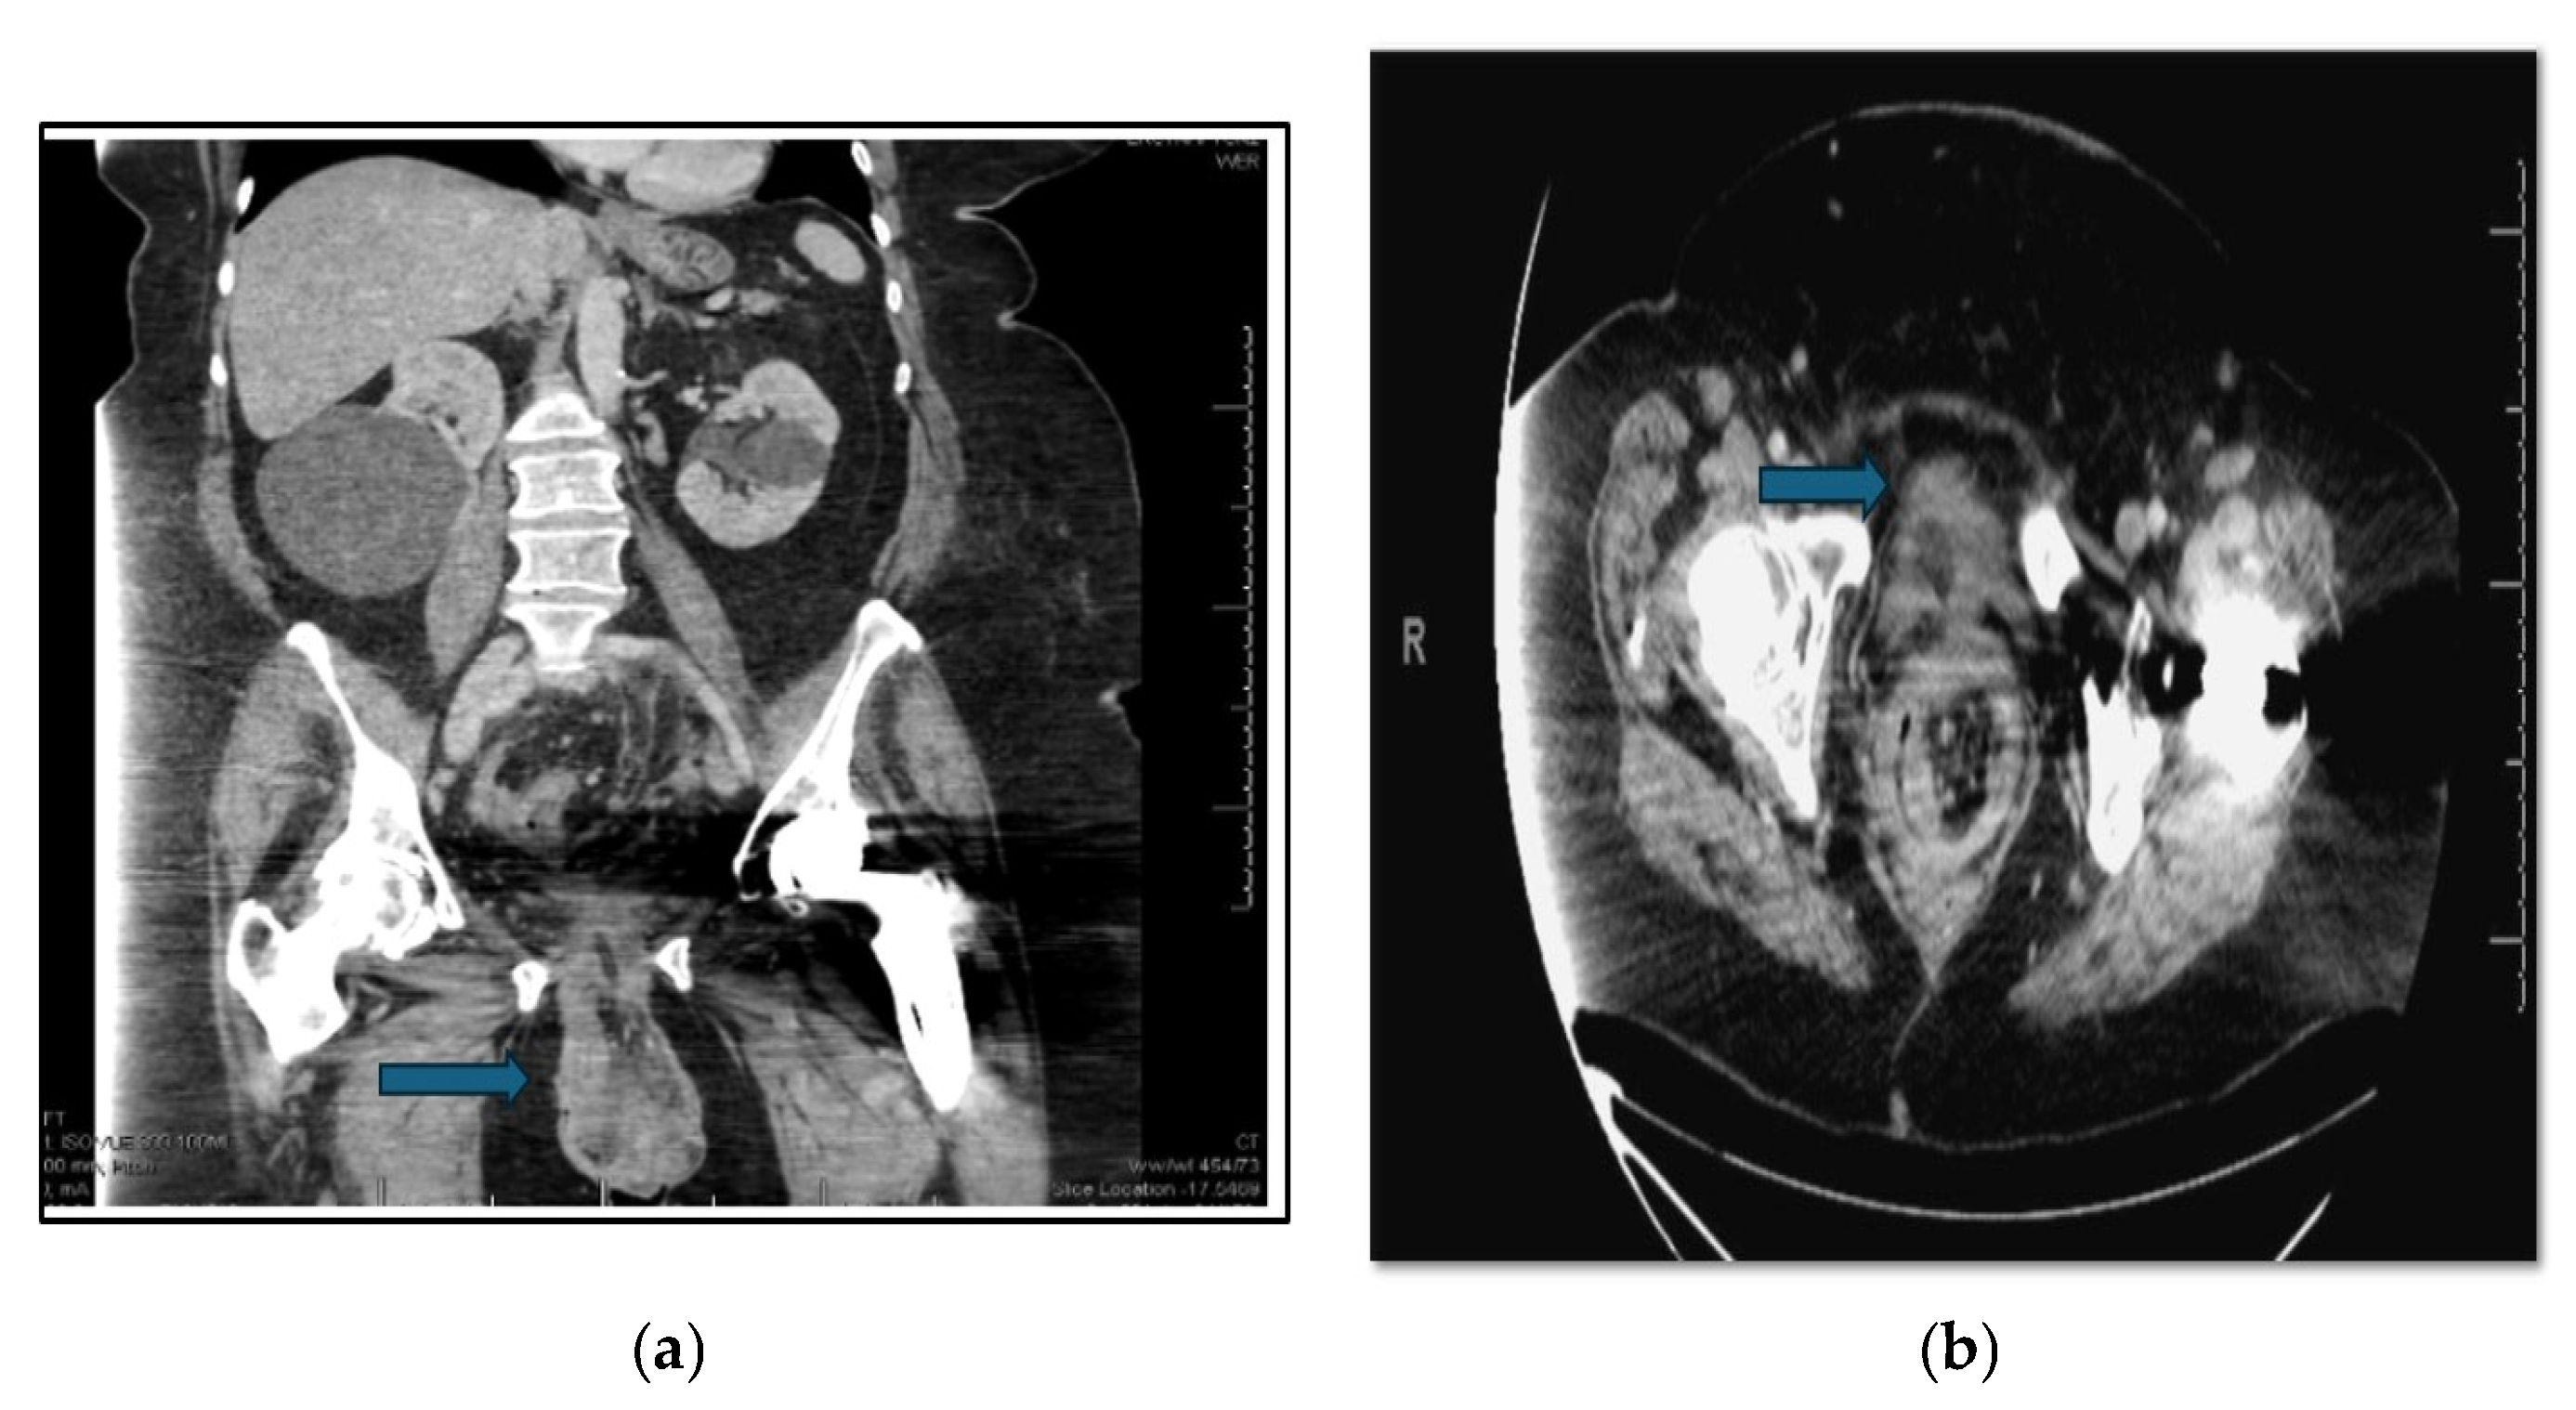

Laboratory results revealed leukocytosis of 13,800 cells/µL, normal lactic acid with subsequent elevation eight hours later to 2.3 mmol/L, hypokalemia with a potassium of 2.6 mmol/L, and acute kidney injury with creatinine 1.1 mg/dL. Urinalysis was consistent with a urinary tract infection, and a urine culture was ultimately positive for greater than 100,000 cfu/mL of Escherichia coli and 50,000–100,000 cfu/mL of Klebsiella pneumoniae. A CT scan of the abdomen and pelvis revealed a large vaginal prolapse containing a segment of the distal sigmoid colon twisted upon itself, consistent with a volvulus. Associated findings included pericolonic fat stranding, bowel wall thickening, and hyperenhancement, suggestive of ischemia. Additionally, the inferior bladder appeared herniated within the prolapse (Figure 2a,b).

Figure 2. (a) Axial CT scan of the abdomen and pelvis demonstrates prolapsed loops of large bowel in the vagina. The blue arrow indicates eviscerated bowel. (b) Coronal view CT abdomen and pelvis scan, and blue arrow showing the prolapsing loops of large bowel.